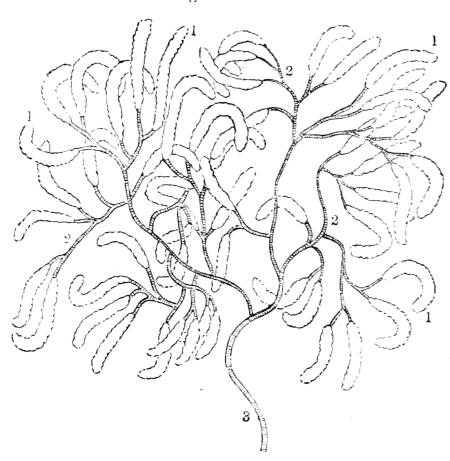

1. The trachea. 2. The right and left bronchus; the left

bronchus showing its division into smaller and smaller

branches in the lung, and the ultimate termination of the

branches in the air vesicles. 3. Right auricle of the heart.

4. Left auricle. 5. Right ventricle. 6. The aorta arising from

the left ventricle, the left ventricle being in this diagram

concealed by the right. 7. Pulmonary artery arising from

the right ventricle and dividing into, 8. The right, and

9. The left branch. The latter is seen dividing into smaller

and smaller branches, and ultimately terminating on the

air vesicles. 10. Branches of one of the pulmonary veins

proceeding from the terminations of the pulmonary artery

on the air vesicles, where together they form the net-work

of vessels termed the Rete Mirabile. 11. Trunk of the

vein on its way to the left auricle of the heart. 12.

Superior vena cava. 13. Inferior vena cava. 14. Air vesicles

magnified. 15. Blood-vessels distributed upon them.